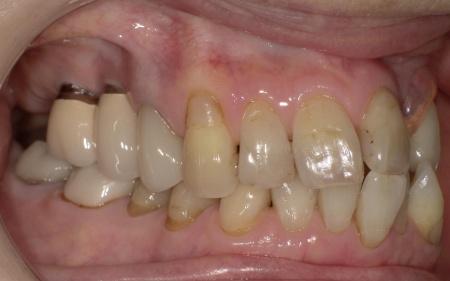

70代女性 歯根が折れた歯を抜いて金属バネを使用しない部分入れ歯で補った症例

「被せ物が装着されている左上奥歯で固いものを噛むと痛む」とご相談いただきました。

拝見したところ、左上の歯(第2小臼歯)が欠損しており、この部分を補うために、両隣の歯を土台として橋を渡すように連結した被せ物「ブリッジ」が装着されていました。

レントゲン撮影をして詳しく検査した結果、ブリッジを支えている左上の歯(第1小臼歯)は、歯根が割れていることが判明しました。

このまま放置すると、周囲の骨や歯茎に炎症が広がるおそれがあります。また、歯の状態から温存は困難だと判断しました。

以上のことから、歯根が折れた歯を抜いたうえで、欠損部位を補う治療が必要だと診断しました。

第1小臼歯に歯根破折を認めました。